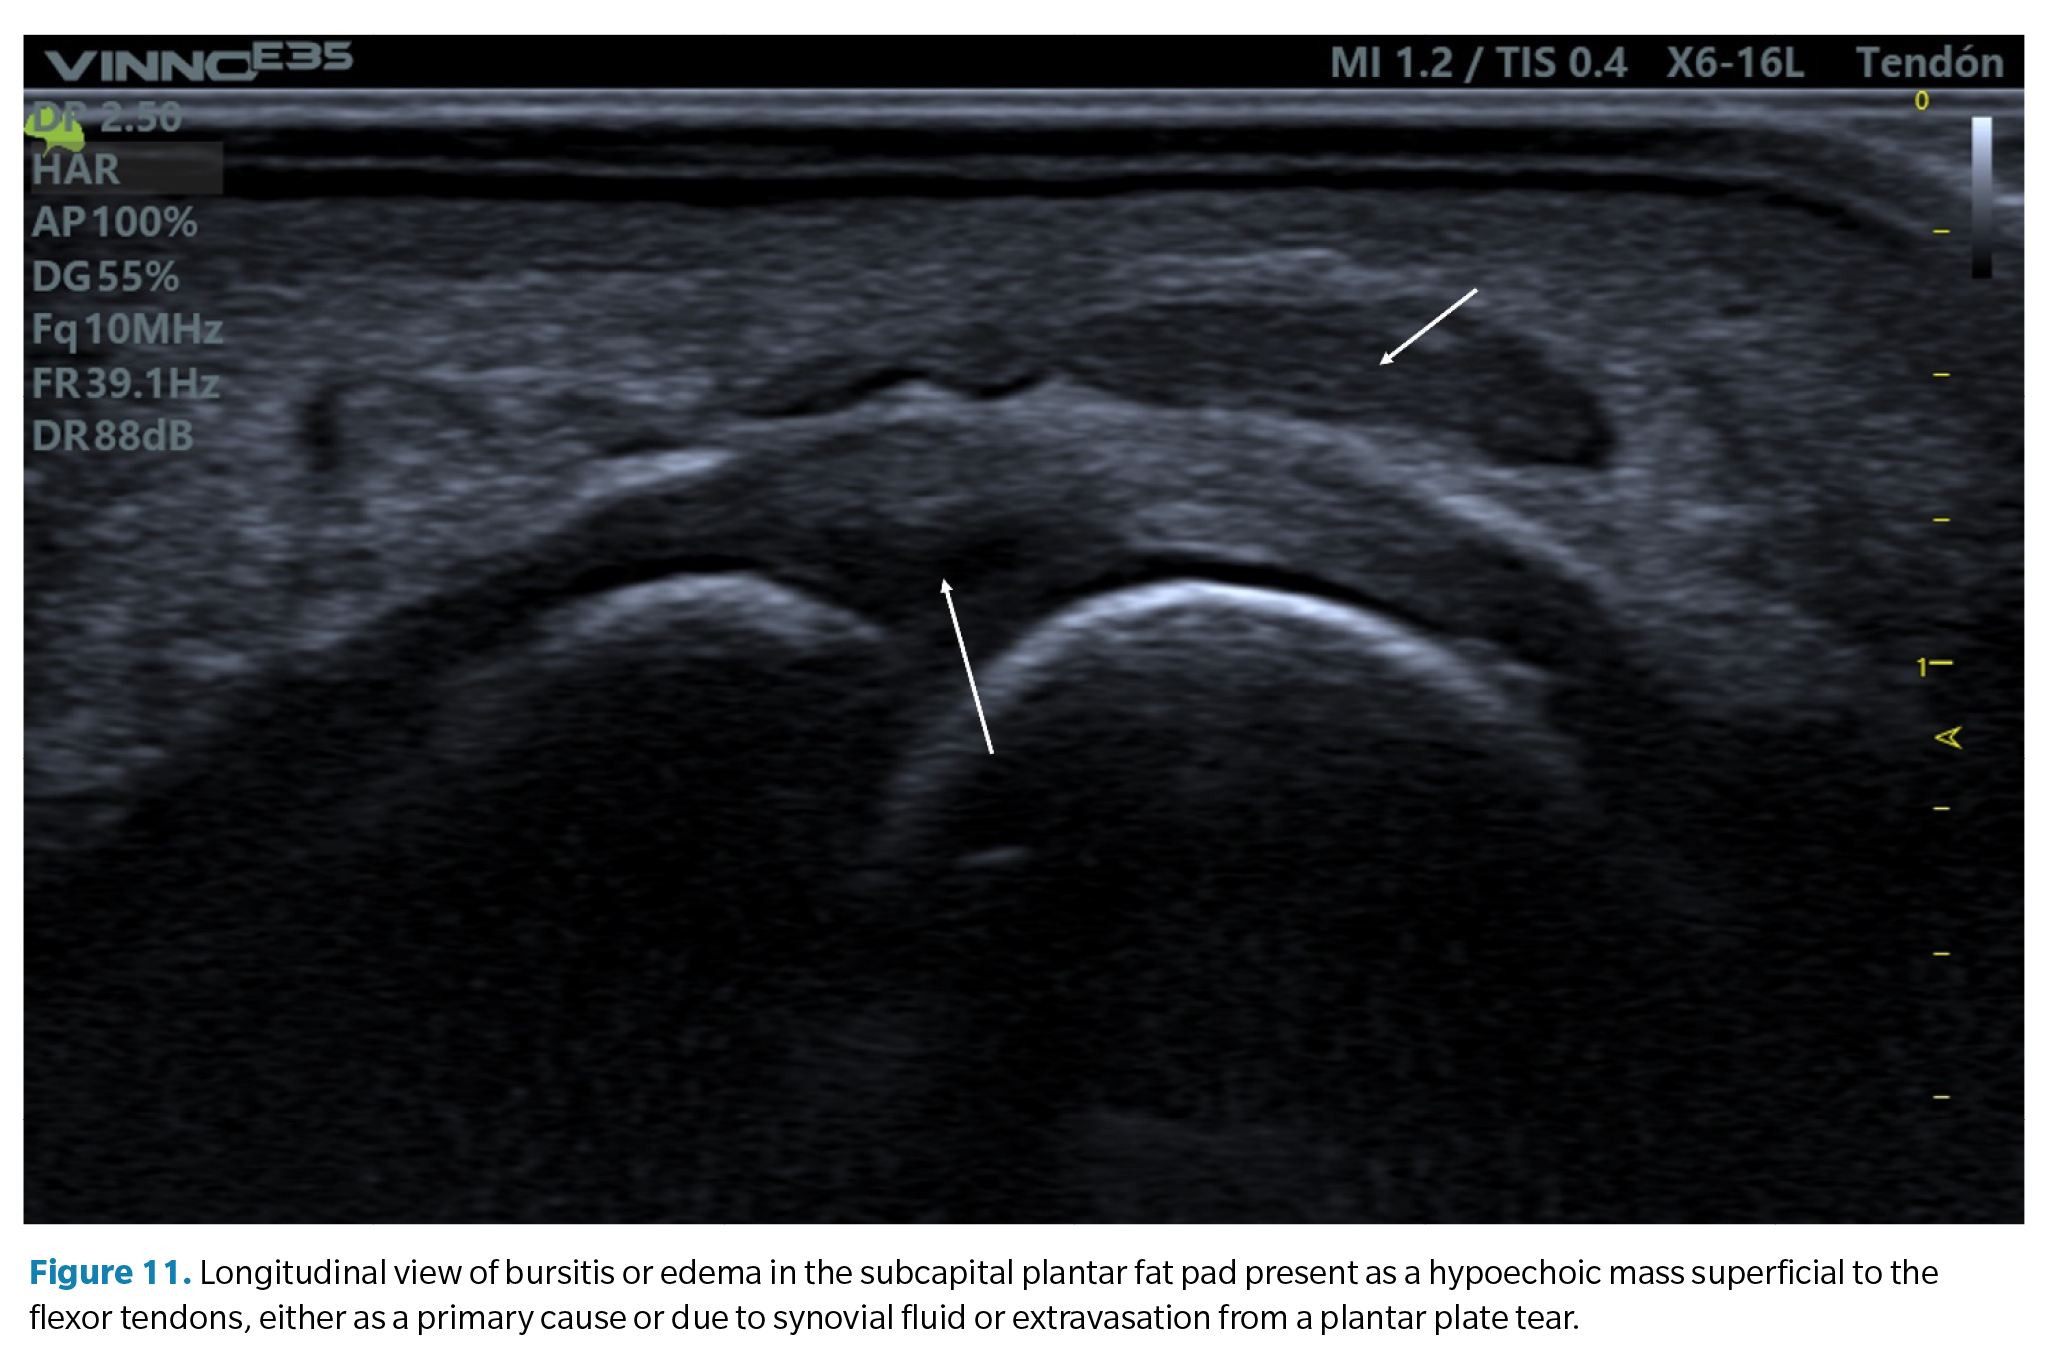

2. Bursitis of the plantar fat pad. In relation to the previous finding, some cases of plantar plate tears may also be accompanied by a hypoechoic infiltrate in the adjacent plantar fat pad. This may be a primary defect due to excessive compression of the fat (compression which is also part of the compressive injury etiology of the plate) or the result of a synovial fluid infiltrate due to capsular rupture extravasation as previously mentioned. It is common in these cases to detect a positive <